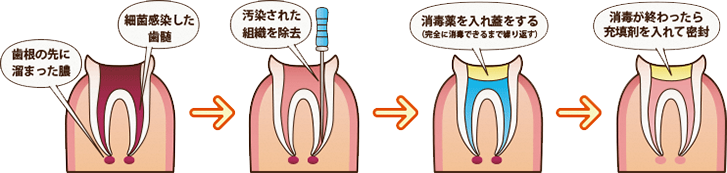

根管治療

むし歯が進行し、歯の神経や歯の根っこの部分まで感染が進んでしまうと、痛みや違和感を強く感じるようになります。そのような場合に必要となるのが「根管治療」と呼ばれる歯の根っこの部分を治療する方法です。

狭い歯の根っこの部分にある神経を取り除き、洗浄と消毒を繰り返し炎症をしずめていくもので、何度か通院が必要となりますが、ご自身の歯を残すためにも根気強く治療を続けていきましょう。